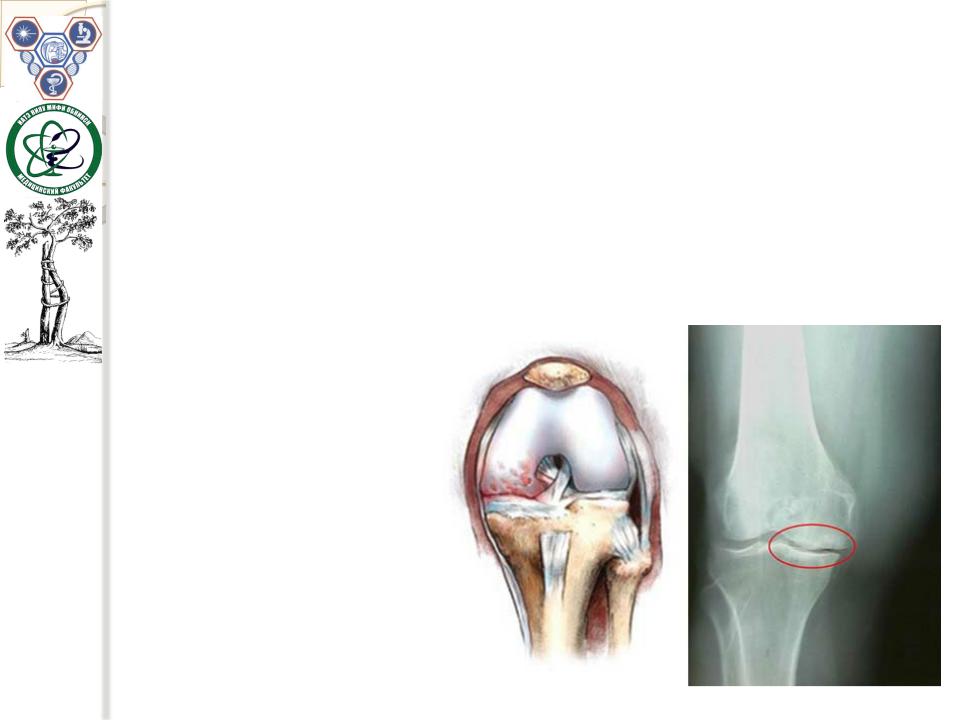

Рентгенологическое

исследование

Нужны3проекции:фас, профильиприсогнутом коленномсуставепод угломв60градусовсо стороныверхнегокрая надколенника. Надколенно-бедренный артроз— изолированное сужениесуставнойщели междунадколенником и бедром(дляэтогоинужна 3-япроекция).

2.Остеофитыи/илисубхондральныйсклероз,субхондральныекисты.

3.Сужениещели бедренно-большеберцовогоилибедренно- надколенниковогосочленения.

Остеонекрозмыщелка бедрасотделениемкостногосегмента(при бедренно-большеберцовомартрозе).